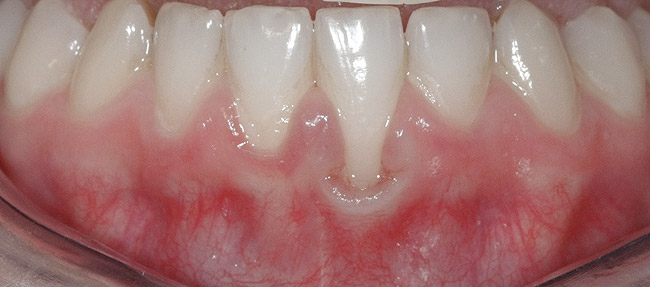

Fig 9. Post-orthodontic Miller Class II recession treated with surgical coverage only in spite of the incorrect inclination of the affected tooth. Clinical view immediately post-orthodontic treatment.

Figure 9